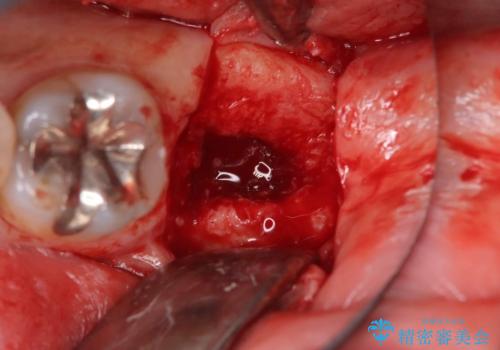

検査の結果、左下7番は歯周ポケットが8mmと深く、レントゲンでも根尖部から骨が溶けている状態が確認されました。エンドペリオ病変と診断し、精密根管治療による保存か、抜歯をしてインプラントで治療するかをご提案したところ、患者様は抜歯・インプラント治療を希望されました。

また、左下6番は銀歯と虫歯を除去した後、見た目や適合性に優れたオールセラミッククラウンで修復を行いました。